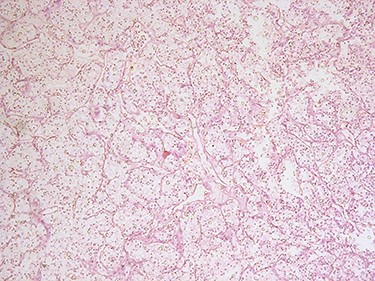

Consequently, the patient was scheduled for Rt radical nephrectomy which was done through Rt transverse paramedian incision. The renal specimen is shown in Fig. 5. The postoperative course went smoothly except for the wound infection which was managed conservatively. Histopathological examination showed that it was clear cell renal carcinoma, grade 2, T3a, free renal vein and lymph nodes were also free from any metastatic deposits (Score0/8; Fig. 6).

H&E microscopic appearance of clear cell renal carcinoma (100 times magnification).